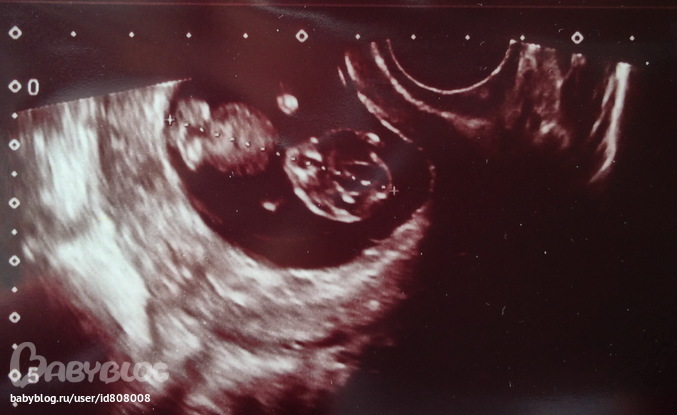

Наше второе УЗИ (11-ая неделька)

УЗИ, КТГ, доплерРовно неделю назад ходили с масиком на 1-ый скрининг, была 11-ая неделька...

Даже картинки они как правило не дают, но мне видимо повезло - врач узи после моего вопроса про получение картинки все-таки напечатала фотку масика, правда маленькую, большая часть фотки черное пятно и где-то слева матка с малышом... но главное, что фотка на руках

Ничего толком правда не понимаю на картинке, только что справа голова, левее тельце, потом ножки согнутые, и ручки вроде сверху и снизу..

Посмотрела размеры - КТР, ШВП и прочие - вроде норма, Г. сказала, что все хорошо, тонуса и прочих бяк нет.....

ага) на фотке - всего 4.3 см...такой масик, и так быстро бъется сердечко :)

155 ударов.... вряд ли пол можно определить...как я поняла до 11-ой недели пульс у малыша от 170-180 ударов, после 11-ой недели падает до 140-160 ударов.... не думаю, что здесь можно как-то определить пол..